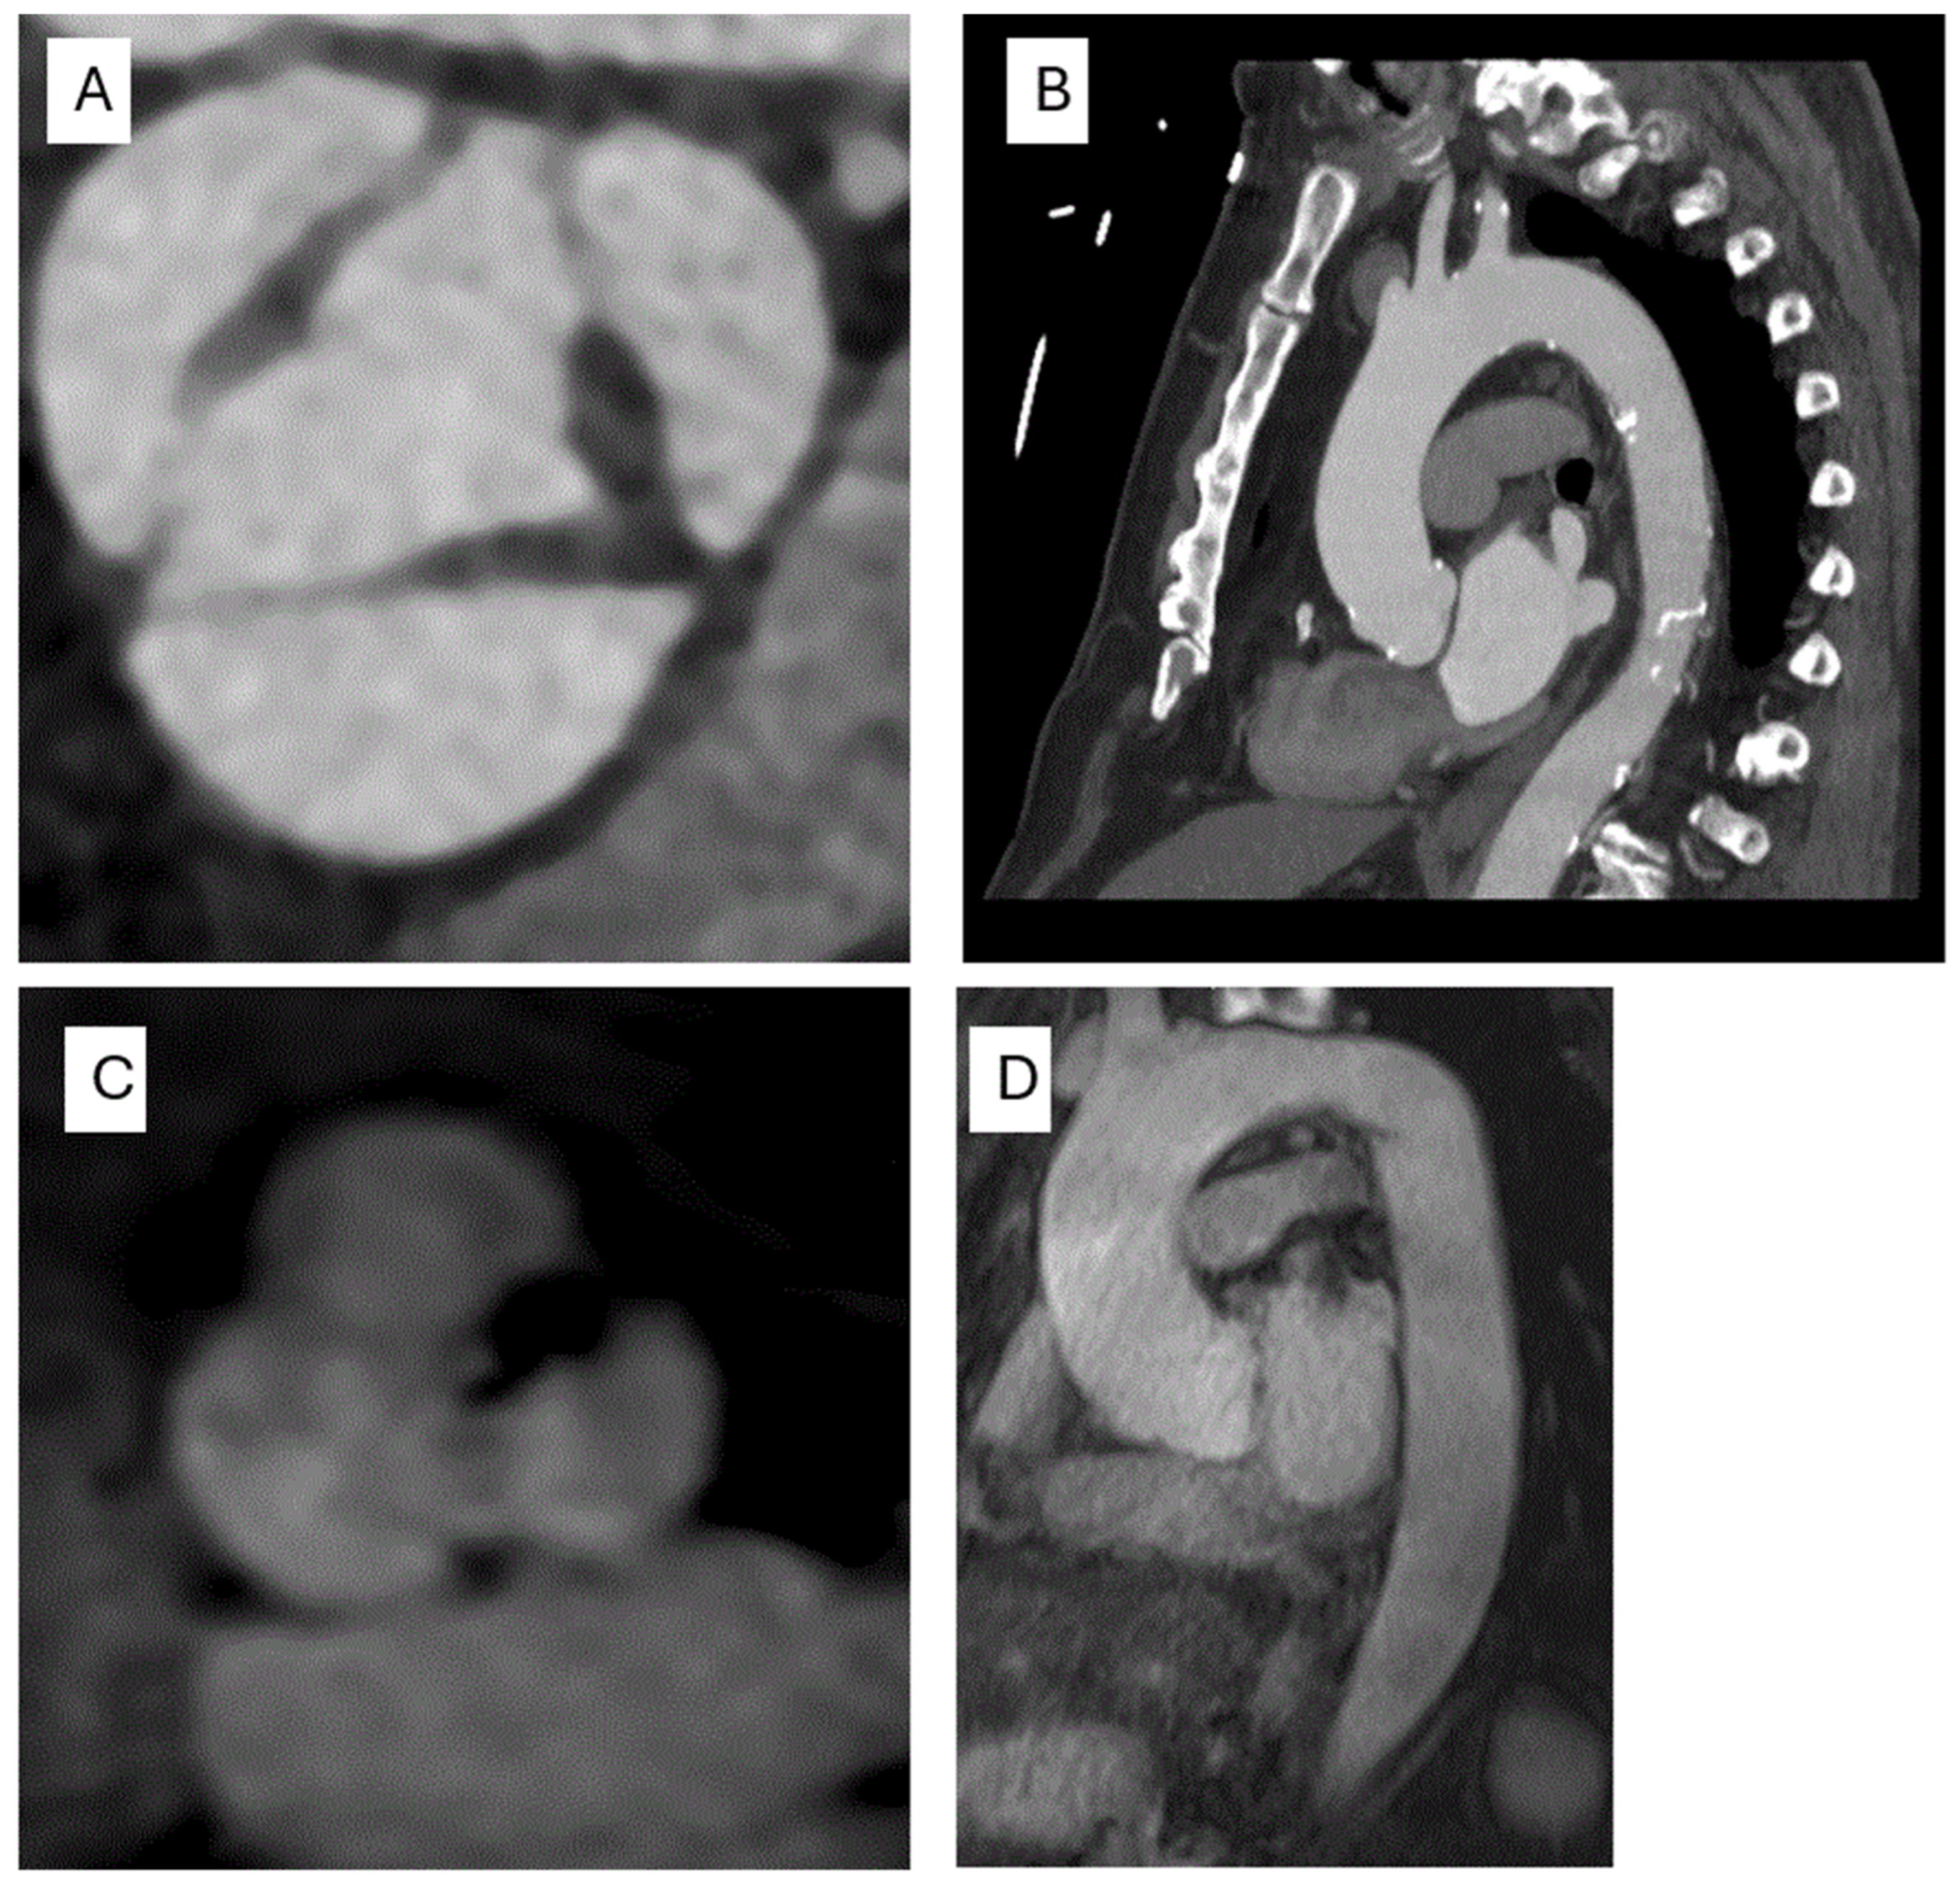

3. The Role of Multimodality Cardiac Imaging in the Evaluation of Aortic Valve Abnormalities and Aortopathy

3.1. Transthoracic Echocardiography (TTE)

3.2. Transesophageal Echocardiography (TEE)

3.3. Computed Tomography (CT)

3.4. Cardiac Magnetic Resonance (CMR)